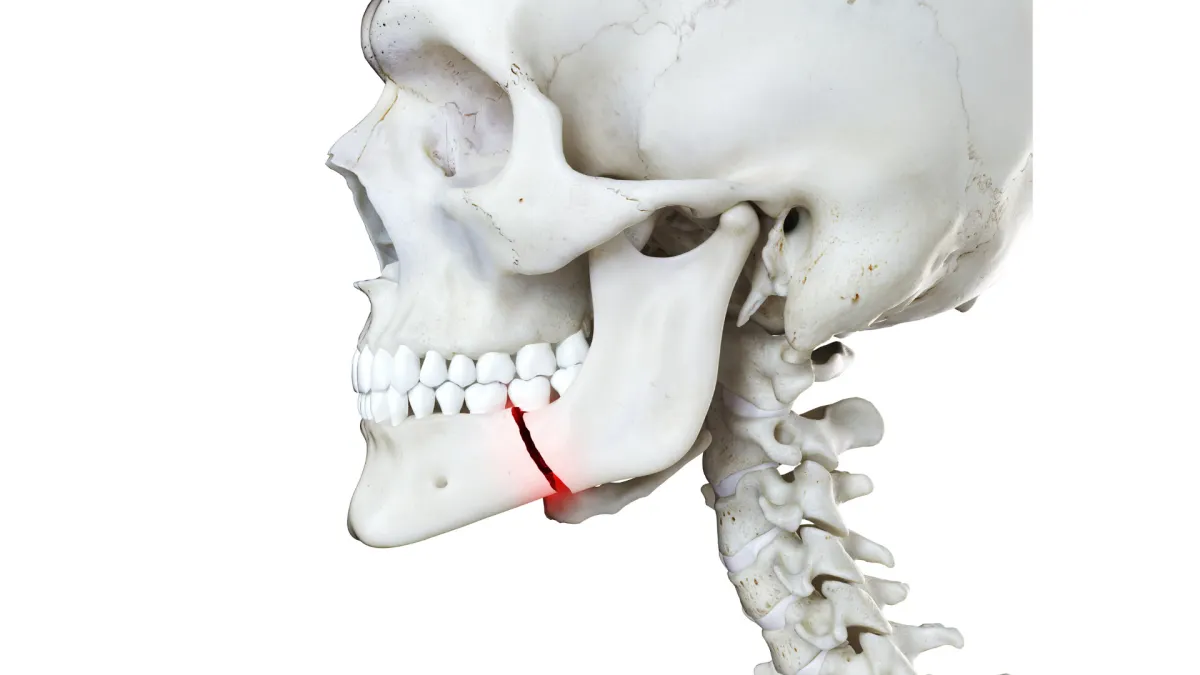

#9 - Injured Your Jaw

A broken jaw is no fun. Basically, there’s nothing you can do for this other than take some over the counter painkillers and put some ice on it until you can get to the ER. You will likely need a maxillofacial surgeon for this and an surgery as soon as possible.